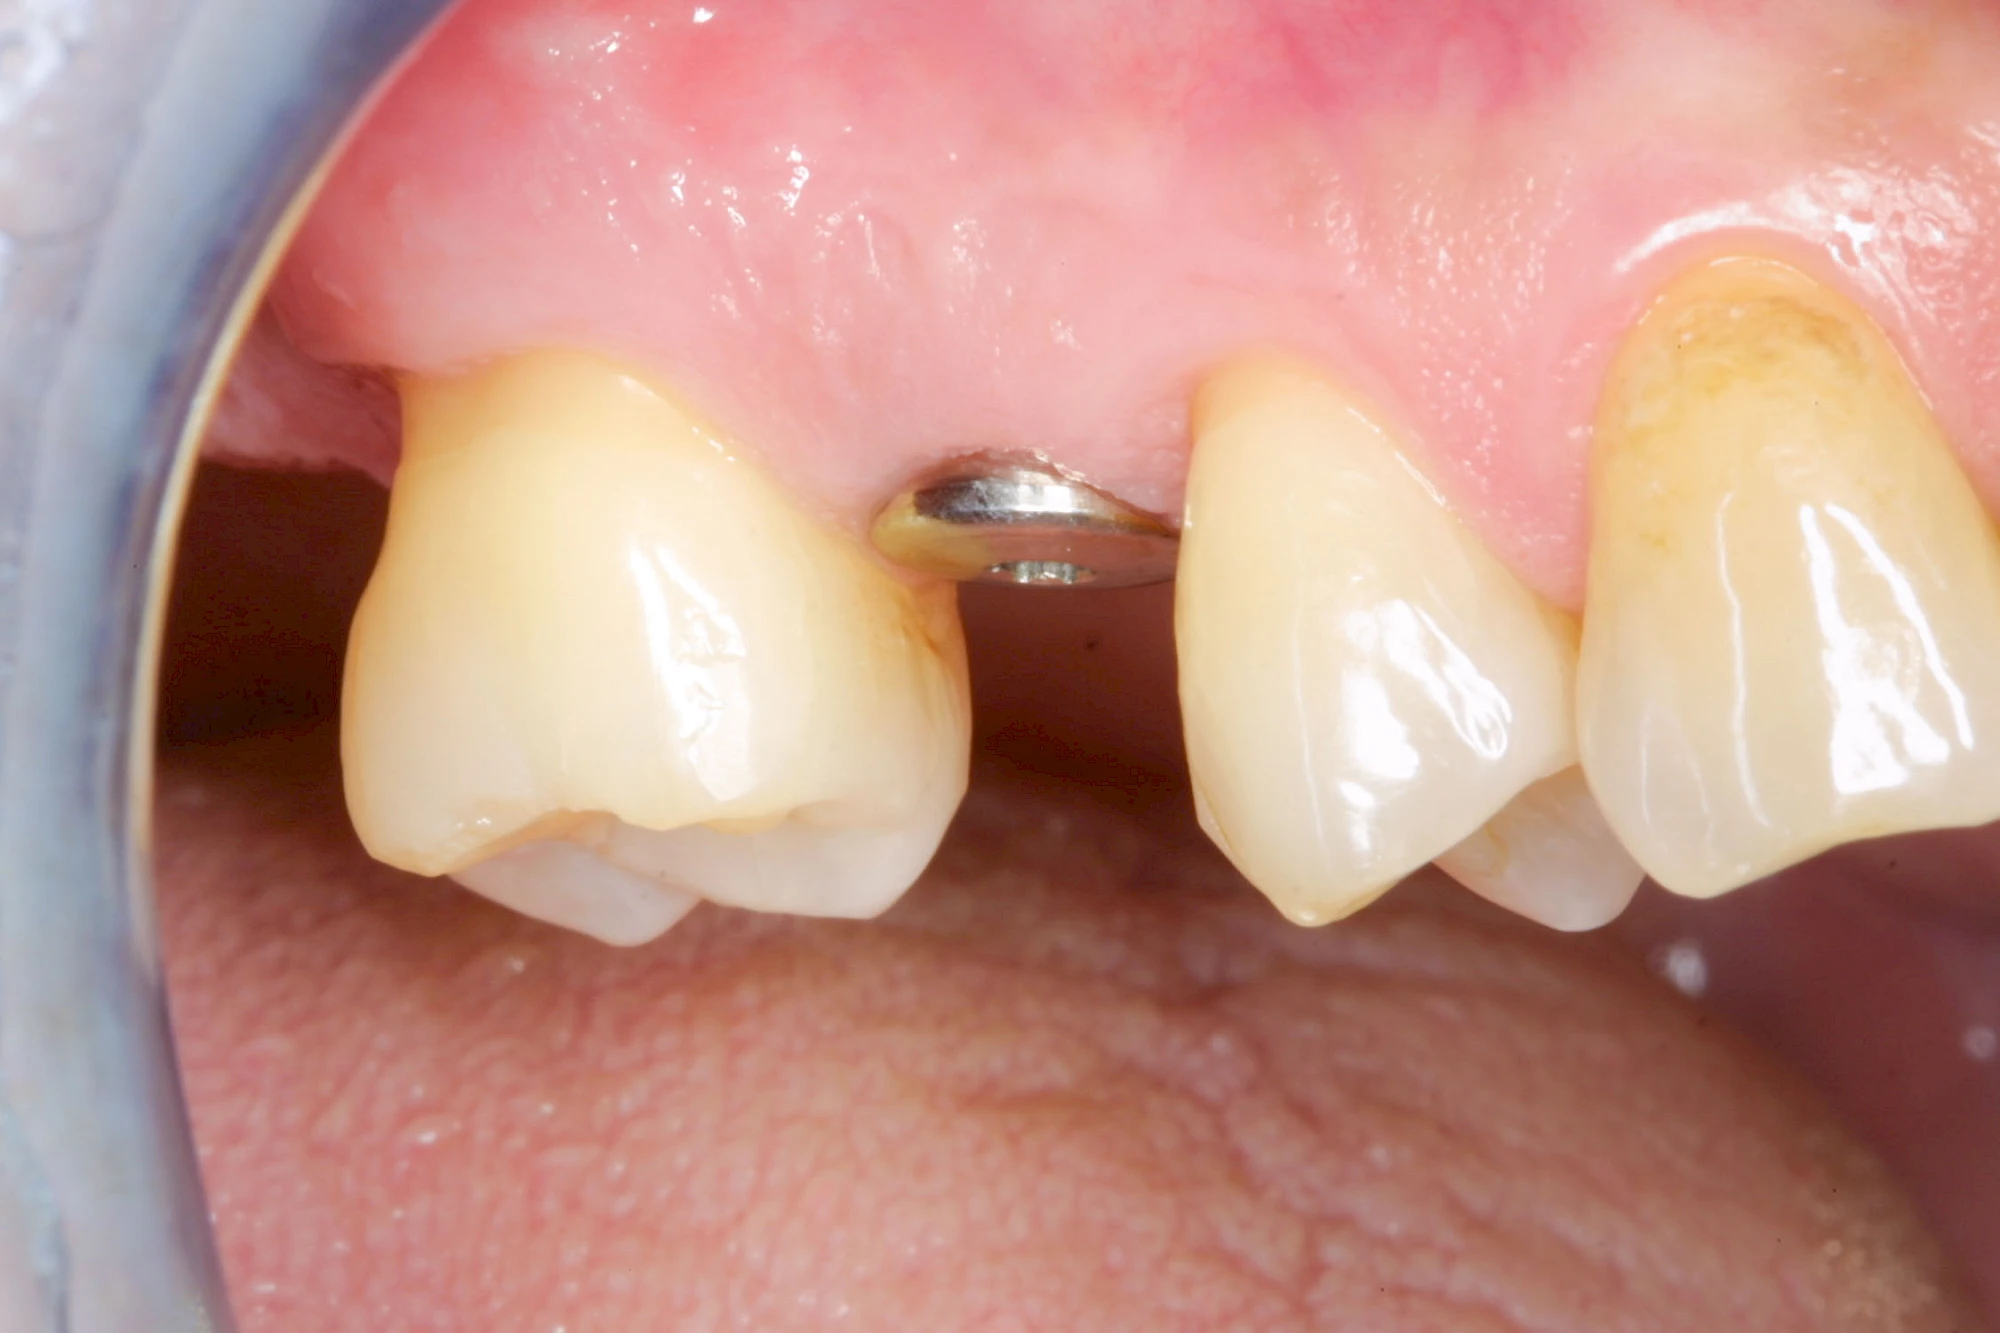

Fehlen einzelne Zähne und die Nachbarzähne sind unbeschadet oder gut zahnärztlich versorgt, werden immer häufiger Implantate gewählt, um die Lücken zu schließen. Auch bei größeren oder verteilten Lücken, wenn keine herausnehmbare Prothese gewünscht ist, werden Implantate für Kronen- bzw. Brückenversorgungen gesetzt. In Einzelfällen entscheiden sich sogar zahnlose Patienten für eine festsitzende Versorgung auf Implantaten.

Varianten zur Verankerung von festsitzendem Zahnersatz auf Implantaten